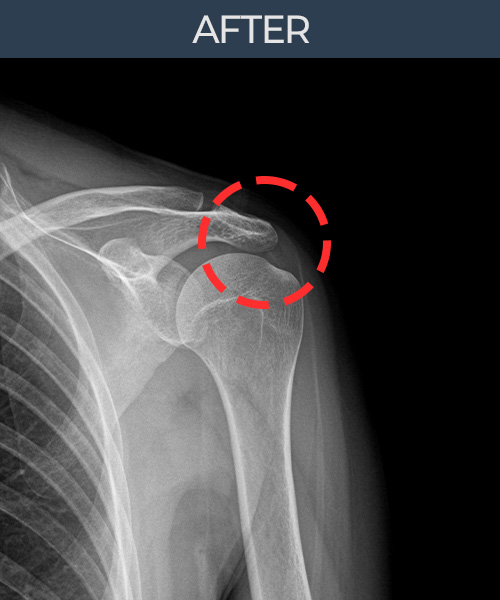

비수술 치료 전후사진

비수술로도 파열된 인대를

물리적으로 재건해 드립니다

본원만의 인대축소봉합술에 사용되는 특허로 보호받는 특수봉합사.

플래티넘정형외과에서는 수술없이도 물리적으로

파열된 인대를 재건

하는것이 가능합니다.